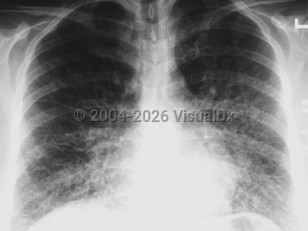

The incubation period for HCPS is 1-6 weeks but usually lasts for 2 weeks. Initial symptoms include the sudden onset of 3-5 days of fever, dry cough, fatigue, dizziness, myalgia, headaches, chills, nausea, vomiting, and abdominal complaints. The gastrointestinal symptoms can at times be severe and mimic surgical emergencies such as appendicitis, cholecystitis, or diverticulitis. Arthralgias and back pain occur less frequently. The disease progresses rapidly to fever, severe coughing, dyspnea, tachypnea, tachycardia, rales, diffuse pulmonary edema, acute respiratory distress syndrome (ARDS), and death. Rarely, some patients may develop disseminated intravascular coagulation (DIC). At the time most patients seek medical care, they usually require immediate intubation and mechanical ventilation.